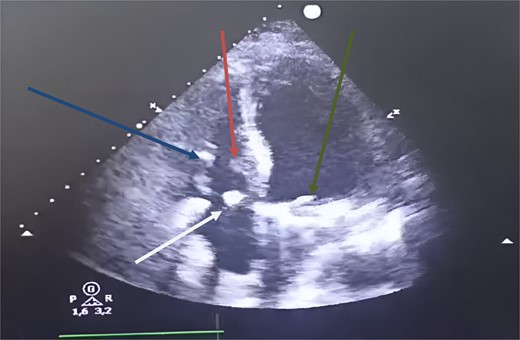

Transthoracic echocardiography (TTE) revealed a mitral valve with moderate, eccentric, double-jet regurgitation, perforation of the anterior mitral leaflet, and the presence of vegetation on the atrial side of the anterior mitral leaflet, which was pedicled, mobile, and measuring 15 × 7.6 mm. The tricuspid valve had vegetation interfering with valve closure, measuring 21 × 12 mm, causing significant central tricuspid regurgitation, with a systolic pulmonary artery pressure (SPAP) at 64 mmHg (Fig. 1).

Transthoracic echocardiography images. (A) Vegetation attached to the atrial side of the anterior mitral leaflet measuring 15 × 7.6 mm. (B) Significant mitral regurgitation. (C) Vegetation attached to the free edge of the anterior tricuspid leaflet measuring 21 × 12 mm. (D) Massive tricuspid regurgitation.